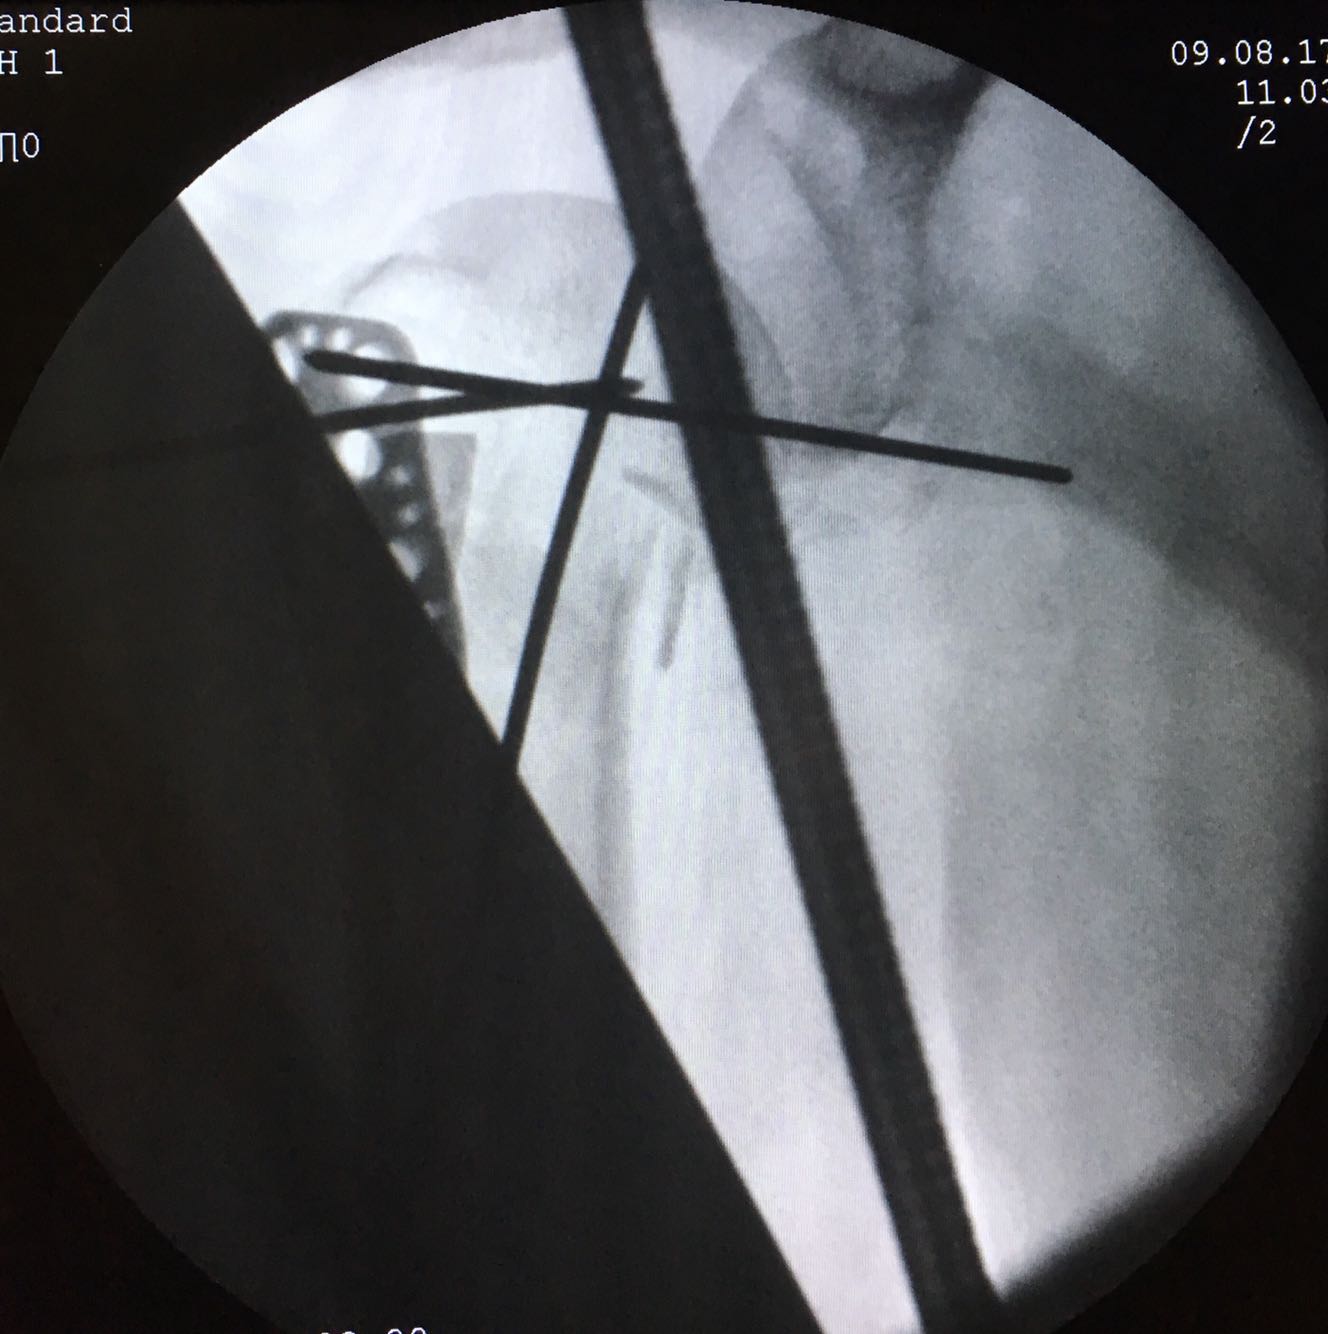

诊断:右肱骨近端骨折 治疗:臂丛备全麻下行右肱骨近端骨折切开复位内固定术,手术过程顺利,麻醉完全,骨折部位复位良好。